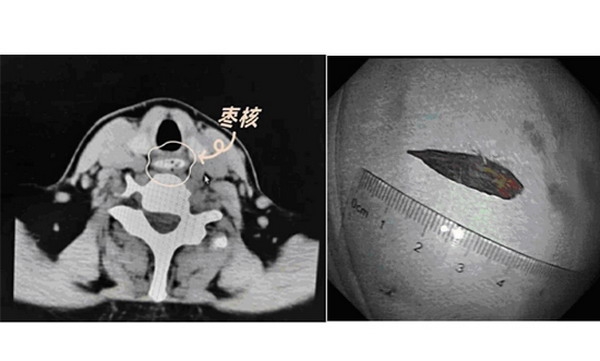

食管內(nèi)異物,通常指人們?cè)谶M(jìn)食過(guò)程中,不慎誤咽魚(yú)刺、骨片、棗核、假牙、硬幣等異物并卡在食管中,既吐不出來(lái)、又咽不下去,造成食管?chē)?yán)重不適或損傷的一種常見(jiàn)急癥。這種急癥往往會(huì)危及人們的身體健康,輕者造成吞咽困難、疼痛咳嗽、惡心嘔吐、反流等不適反應(yīng),重者造成食管損傷,甚至殃及食管周?chē)难堋夤芎徒M織。就食管內(nèi)異物的危害和正確處置,我們邀請(qǐng)了曲阜市人民醫(yī)院醫(yī)學(xué)影像科醫(yī)師、市紅十字會(huì)應(yīng)急救護(hù)培訓(xùn)師孫  偉同志為大家作科普。

2.植物類(lèi)異物:如棗核、話梅核、櫻桃核等;

不同的地域、不同的飲食習(xí)慣,常見(jiàn)的食管異物的種類(lèi)和比例也不盡相同,在我國(guó)北方以棗核和骨類(lèi)常見(jiàn),南方沿江沿海地區(qū)則以魚(yú)骨、蝦、貝殼等常見(jiàn)。

這些食管異物中,比較尖銳的異物?如魚(yú)刺、雞鴨骨頭、帶尖的果核等,易刺傷食管黏膜?;體積較大的異物?如硬幣、假牙、玩具的零部件等,易卡在食管狹窄處?